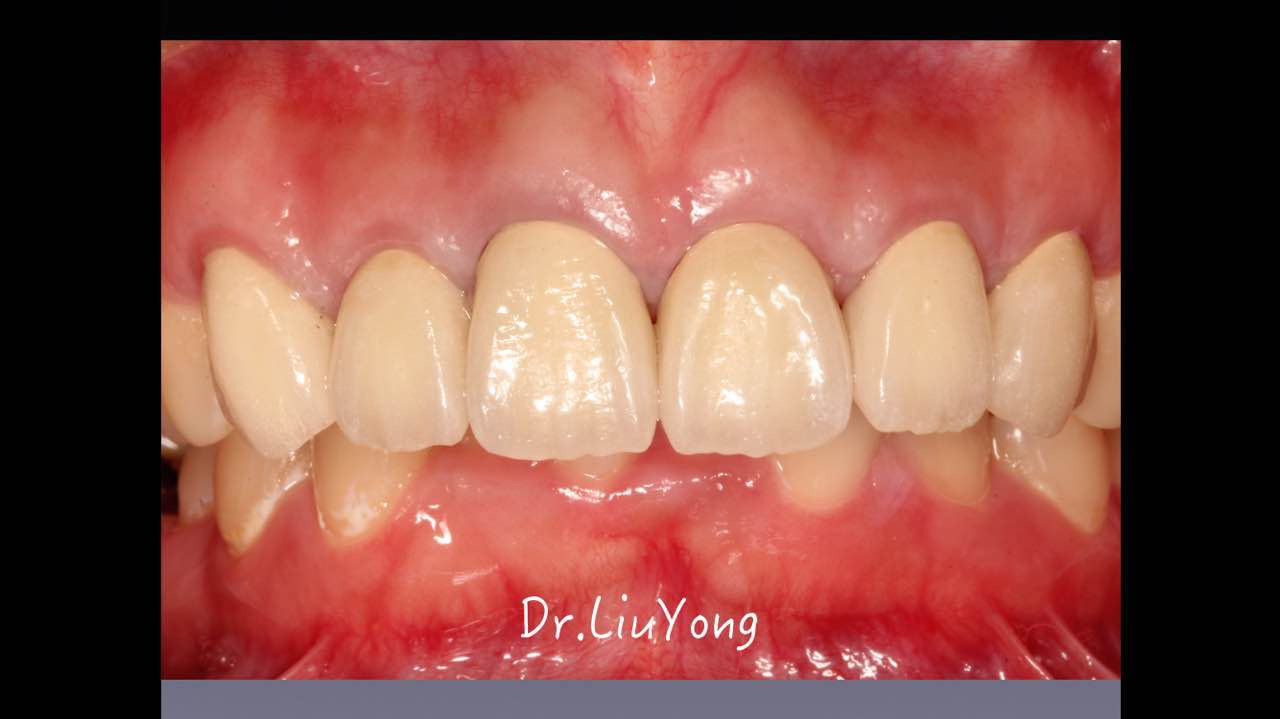

嚴(yán)重破壞生物學(xué)寬度,根尖瘺管,重行根管治療, 第一次冠延長建立唇腭側(cè)及鄰面BW,術(shù)后牙齦扇貝形差, 齦乳頭黑三角,再次行美學(xué)冠延長,建立牙齦扇貝形,手術(shù)免費, 患者因經(jīng)濟原因只能選擇鑄樁及鈷鉻合金烤瓷冠。終于完工